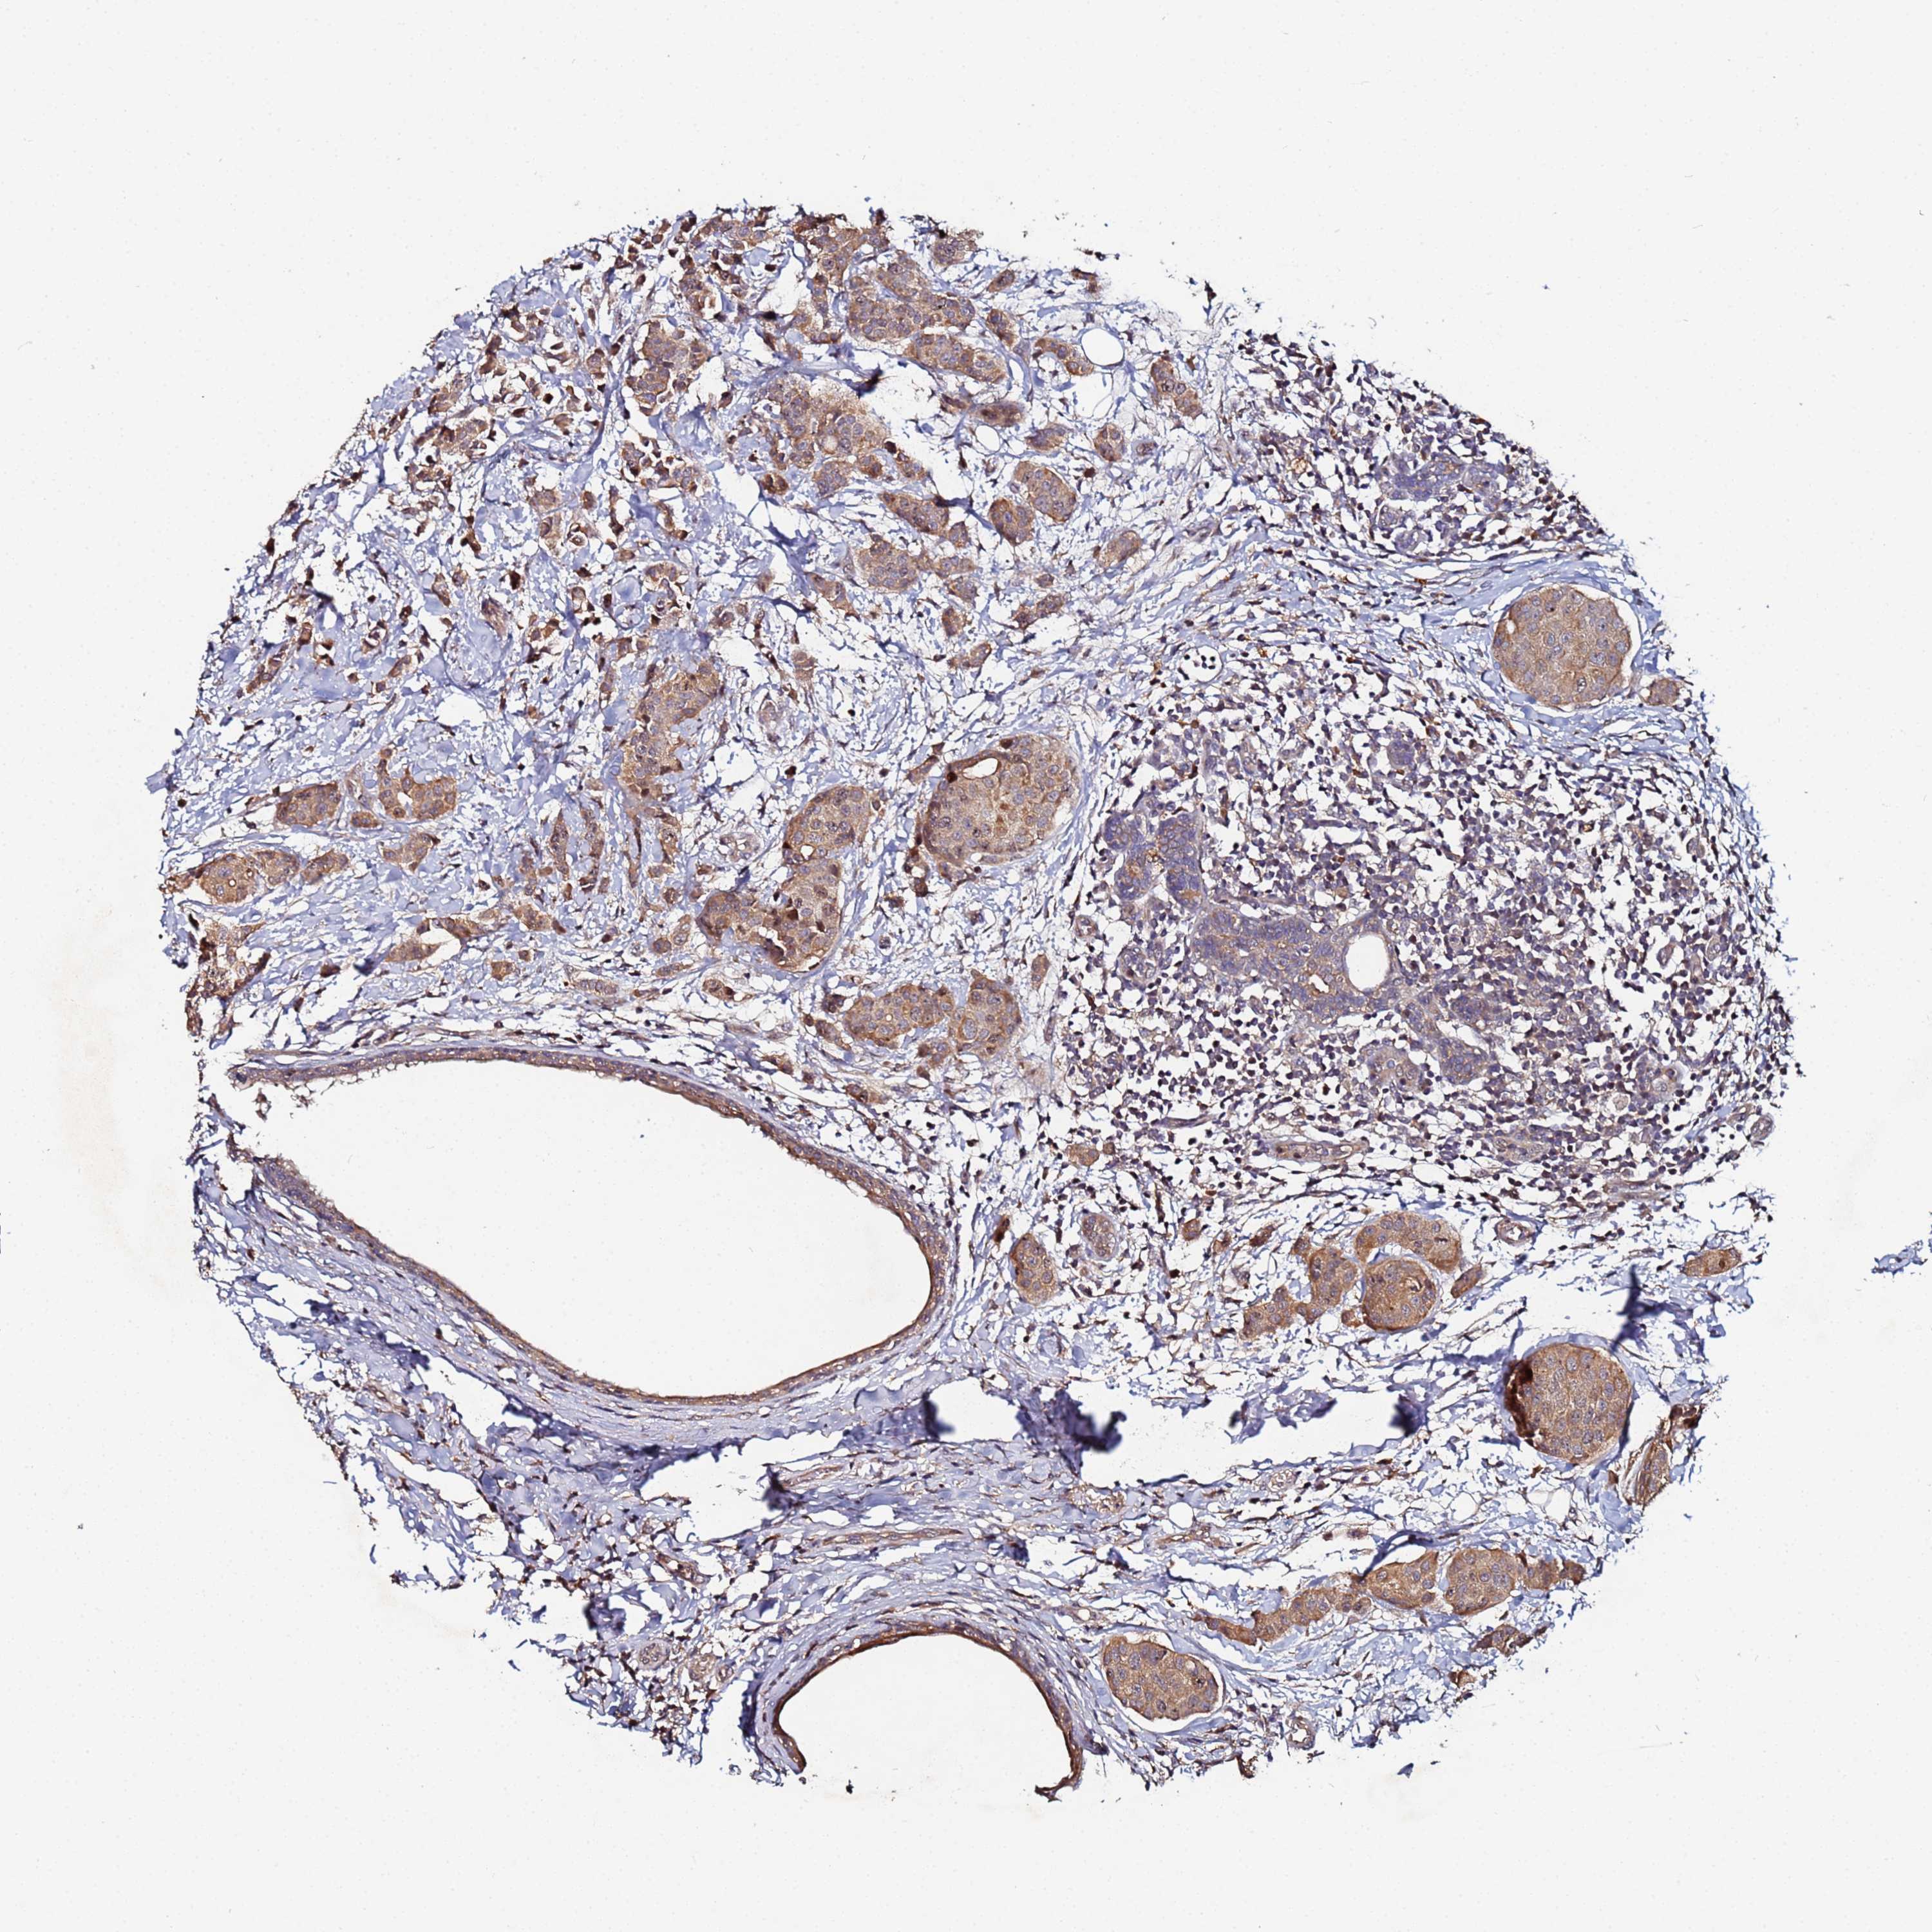

CANCER BREAST CANCER Show tissue menu

BRCA TCGA BRCA VALIDATION PROTEIN EXPRESSION